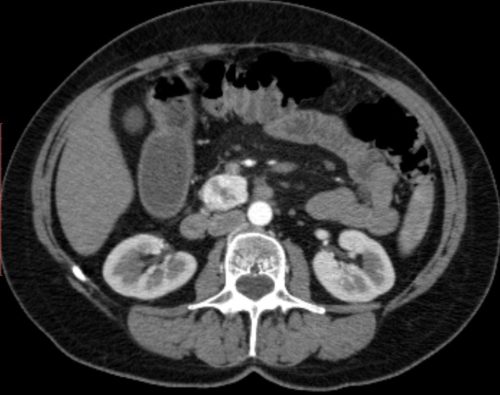

КТ при панкреатите дает возможность четко дифференцировать плотные панкреатические массы от жидкостных образований, абсцессов, псевдокист. При панкреонекрозе эластичность сосудов снижается, в результате чего появляются гипо- и аваскулярные области.

КТ при панкреатите

При панкреонекрозе контуры ПЖ неровные, структура неоднородна за счет формирования секвестров, в парапанкреатической клетчатке могут выделяться абсцессы. Всем больным с деструктивным панкреатитом в конце 2-й недели заболевания показана КТ для выявления парапанкреатита и локализации гнойников.

При хроническом панкреатите большое значение имеет КТ с контрастированием. Одними из основных признаков хронического поражения железы, выявляемых при КТ, являются кальцинаты паренхимы, внутрипротоковый калькулез, кистозная трансформация. Кисты ПЖ выглядят как полостные формирования с меньшей плотностью, чем кровеносные сосуды, с выраженной стенкой различной толщины зависимо от стадии ее формирования.

В артериальной и венозной стадии контрастирования возможно дифференцировать хронические панкреатиты от опухолевых поражений.